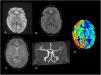

Magnetic resonance imaging at the level of the cerebellar hemispheres. A) diffusion sequence, B) FLAIR sequence, C) gradient echo sequence and D) TOF angiography revealing no abnormalities. E) Decreased blood flow in right cerebellar hemisphere in ASL perfusion sequence.

ASL, arterial spin labelling: FLAIR, fluid-attenuated inversion recovery; TOF, time of flight.

A right-handed girl aged 7 years presented to our hospital with an episode of generalised muscular rigidity with jerking movements in the right upper extremity, disconnection syndrome and relaxation of sphincters. The patient received intravenous benzodiazepines in the emergency department, which achieved resolution of the seizures. Since the patient continued to have a low Glasgow Comma Scale score, aphasia and immobilization of the extremity, the stroke code was activated. A perfusion magnetic resonance imaging scan performed 2 h after onset showed decreased blood flow in the left hemisphere (Fig. 1) and the right cerebellar hemisphere (Fig. 2), with preserved perfusion in the basal ganglia. The electroencephalogram evinced an abundance of epileptiform discharges in the right-side anterior frontotemporal region. Since Todd paralysis was suspected, an intravenous bolus of levetiracetam was administered to the patient, which achieved full resolution of the symptoms in 24 h.

Todd paralysis, also known as post-ictal paralysis, is a condition of unknown aetiology and variable duration1 manifesting with focal weakness after a seizure,2 although, if it involves the dominant side, it can manifest with aphasia in addition to motor impairment,3 as was the case of our patient, and the main differential diagnosis is stroke. Perfusion imaging can evince a reduction in blood flow that does not match a vascular territory, sparing the basal ganglia, and crossed cerebellar diaschisis due to disconnection secondary to the transient metabolic changes in the contralateral corticopontocerebellar pathway.